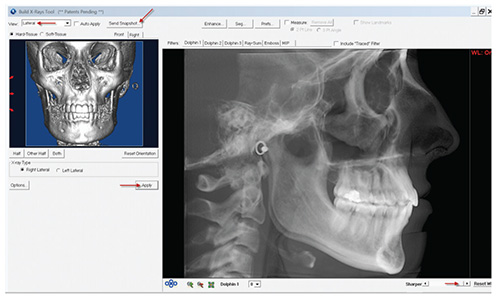

- Click "OK" to exit the "Sinus/Airway" window. Then

click "Build X-rays." Click "OK" in the pop-up window

that appears and the "Build X-rays Tool" window will

open. (See above.)

- Select "Lateral" from the "View" drop-down menu and

click "Apply." Adjust the "Sharper" slider and "Dolphin

1" Level to the doctor's preference. [*Note that the ceph

generation preferences should be selected according to the

desired protocol; orthogonal (1:1) or perspective (magnified)

projection]. Then select "Send Snapshot" and "Save

to Dolphin Layout/Database."

- To save the lateral X-ray image, click the square indicated

below (the "Image Title" will automatically load

with "X-ray Lateral"). Then click "Save."